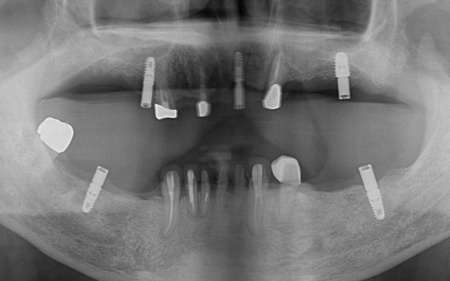

まずは、歯根を支える骨が溶けてなくなる歯周病が進行しており、長期的な維持が難しいと判断した左下奥歯(第2小臼歯)を丁寧に抜きます。

次に、上下左右の奥歯部に1本ずつ、左上前歯に1本、計5本のインプラントを埋入する手術を行いました。

インプラントは、長年多くの症例で使用実績があり、噛む力に耐える強さと骨へのなじみやすさが評価されているオステム社の製品を使用しています。

続いて、残存している上の歯に対しては根管治療を行いました。

ただ、右上前歯(犬歯)は状態が十分に改善せず、温存が困難であると判断したため、抜歯を行いました。